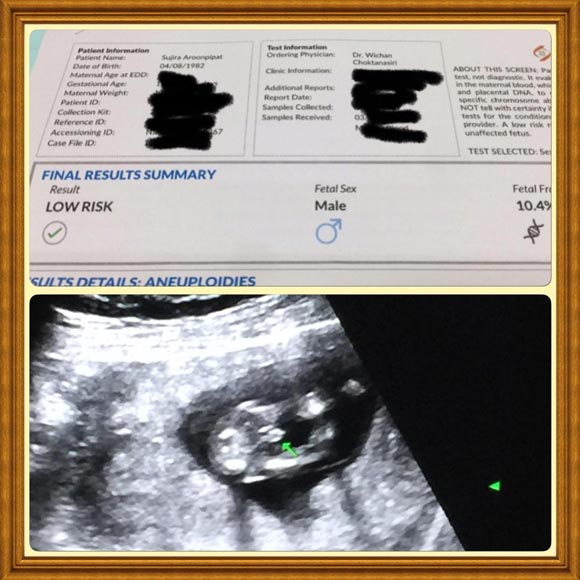

นุ้ย สุจิรา เผยข่าวดีตั้งครรภ์ลูกคนที่สองแล้ว พร้อมเผยภาพอัลตราซาวด์ลูก อายุครรภ์ 3 เดือน ด้านสามีเฮลั่นได้เพศลูกที่ต้องการ

กลายเป็นคุณแม่ลูกสองไปอีกคนแล้ว สำหรับพิธีกรสาวสวยดีกรีนางสาวไทยอย่าง นุ้ย สุจิรา ที่ล่าสุด (5 เมษายน 2560) เจ้าตัวได้ออกมาเผยเรื่องน่ายินดีผ่านอินสตาแกรมส่วนตัวว่า ตอนนี้ตนได้ตั้งท้องลูกคนที่ 2 เป็นที่เรียบร้อยแล้วว่า "เข้าสู่โหมดคุณแม่ลูกสองเต็มตัวค่า #รดาเป็นพี่สาวแล้วน้า"